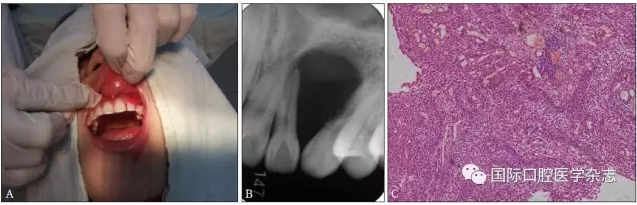

典型病例4 患者因左上頜牙齦長包塊就診,X線片檢查發(fā)現(xiàn)左上頜22—23牙區(qū)明顯的透射區(qū),邊界清楚,相鄰牙根被推擠移位。手術(shù)切除后病理結(jié)果為成釉細胞瘤(圖4)。

A:術(shù)前臨床照片;B:術(shù)前X線片;C:蘇木精-伊紅染色切片,顯示成釉細胞瘤的病理特點 × 100。

圖 4 成釉細胞瘤

Fig 4 Ameloblastoma